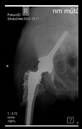

The direction of the cup stem was determined by the guide wire. The aiming device was needed to introduce this wire. After removing the aiming device, the next step was the drilling. Since a cannulated drill bit was used, the previously installed wire could guide the process. A self-positioning reaming tool was then used in the drilled channel. In the prepared cavity, the cup was fitted perfectly. Of the two stemmed cups available to us, the McMinn cup (Waldemar Link, Hamburg, Germany) had the simpler geometry and was therefore chosen. The stemmed cup was inserted according to the manufacturer’s recommendation. In the presence of a significant bone defect, a synthetic bone graft may be impacted for substitution.

The radiological examination allowed us to verify the close bone-to-implant contact and the unchanged position of the implant during follow-up.

In all the cases operated with the above-described targeting procedure, the stems of the cups remained between the cortical bone surfaces without perforation of the linea terminalis, as shown by postoperative radiographs. There were no complicated surgical situations. In 16 cases, the wound healings were uneventful, and the hips were able to bear weight again after postoperative rehabilitation.